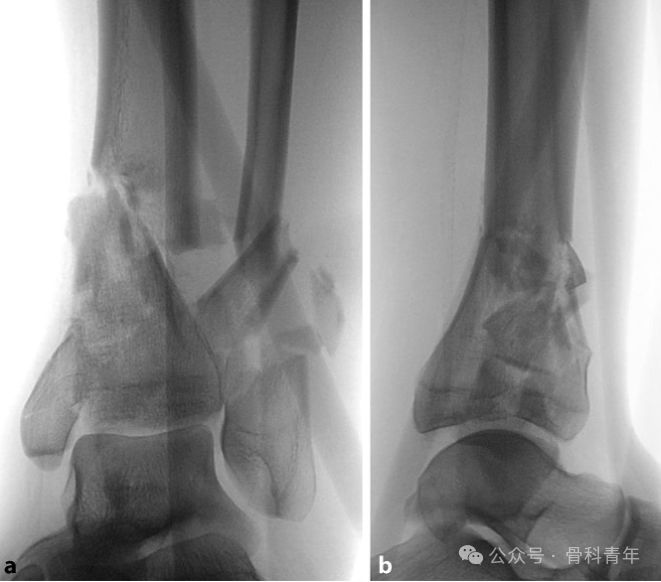

腓骨完整时,胫骨承受轴向压力而发生的骨折(a); -

胫骨内翻畸形,外侧受牵拉力,内侧受压力(b); -

胫骨外翻畸形,外侧受压力(c);